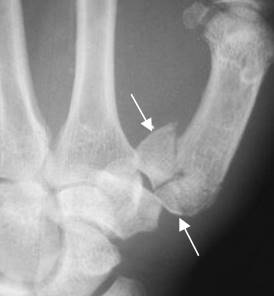

Fig 176. Luxofractura de Rolando.

Rx AP. Luxofractura conminuta en la articulación metacarpofalángica del pulgar, por lesión de Rolando.